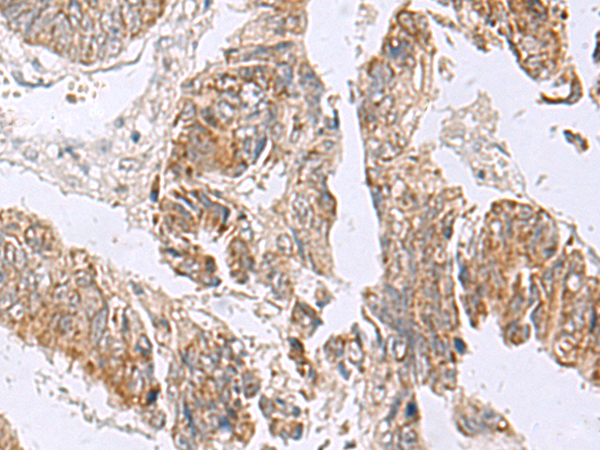

IHC (Immunohistochemistry)

(Immunohistochemistry of paraffin-embedded Human colorectal cancer tissue using RTKN2 Polyclonal Antibody at dilution of 1:75(×200))